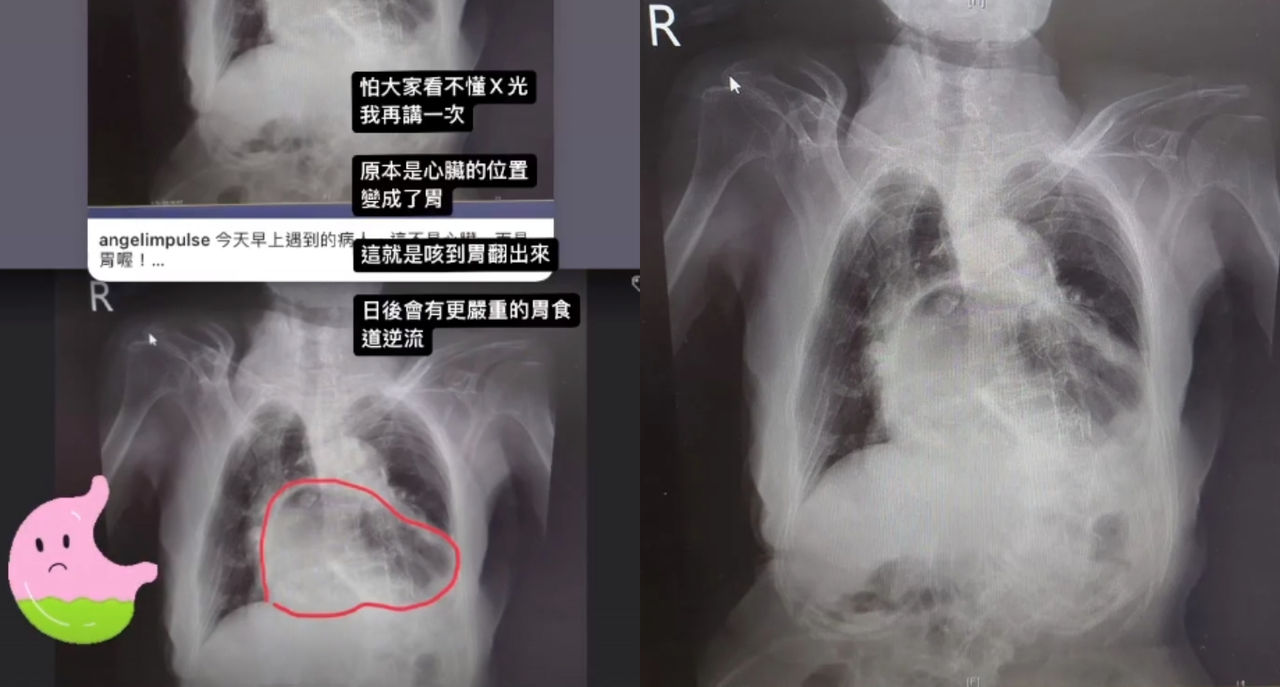

▲姜冠分享一張胸部X光片解釋,這個就是經典的『咳到胃翻出來』。(圖/翻攝自姜冠宇臉書)

姜冠宇今天在個人IG貼出胸部X光片解釋,「今天早上遇到的病人,這不是心臟,而是胃喔!」他說明這就是經典的「咳到胃翻出來」病例。姜冠宇補充說,怕大家看不懂X光,「我再講一次,原本是心臟的位置,變成了胃」,這就是咳到胃翻出來,日後會有更嚴重的胃食道逆流。

姜冠宇表示,這就是所謂胃疝脫,錯位突破橫膈膜擠入胸腔。他解釋,若遇到這種情況,就這只能手術,縫補橫膈膜,不過該名病患已經不願意手術,那就只能出院每天吃一點點。

姜冠宇強調,這不能只有專注在消化道的問題,因為這不可能1、2次嗆到就咳成這樣,明顯是很長期的咳嗽問題,是不是背後有其他的慢性呼吸道疾病像COPD或氣喘,甚至是潛在感染後的後遺症也要評估和給治療,不然沒得改善還會更嚴重。